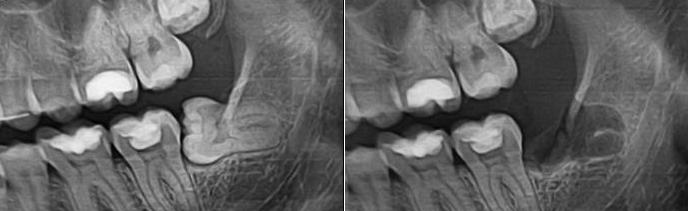

Удаление нижнего зуба мудрости: фото до и после